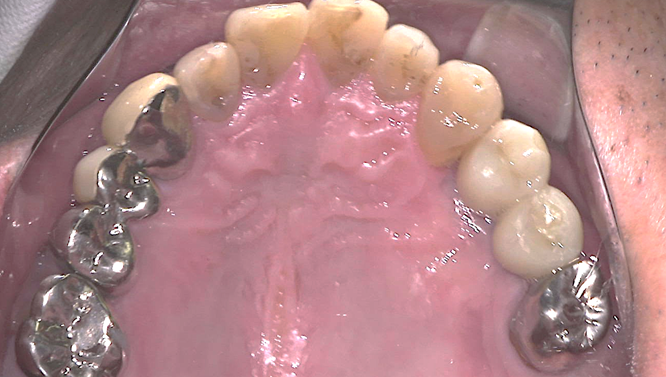

①歯根破折により右上小臼歯が動揺し、歯肉が腫れてしまい、周囲の歯槽骨が吸収していてインプラント埋入

が出来ないと他院で診断され、当院にインプラント治療を希望されました。

予定通りジルコニアクラウンにて、インプラント修復が行えました。